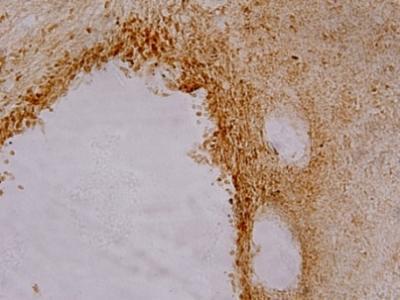

This is immunohistochemistry showing normobaric oxygen pretreatment increased the expression of Notch-1 in the cerebral cortex of rats with focal cerebral ischemia.

(Photo Credit: Neural Regeneration Research)